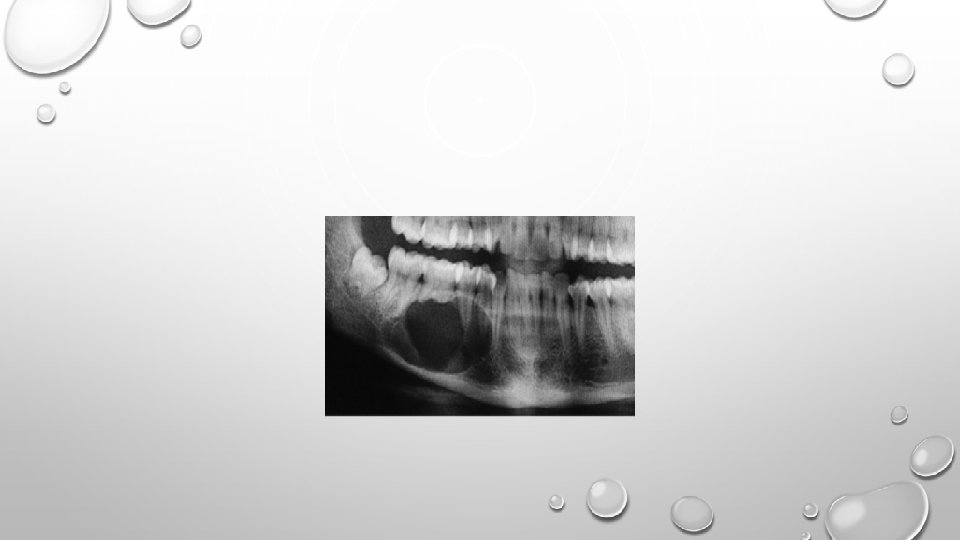

AMELOBLASTOMA: • It is an odontogenic tumor representing approx. 11% to 13% of the odontogenic tumors. • It is bony-hard and non-tender on palpation. • Unicystic or mural ameloblastoma forms in the wall of a dentigerous cyst. • Radiographically, a unilocular or multilocular radiolucency is seen. Soap-bubble or honey-comb appearance is characteristic.